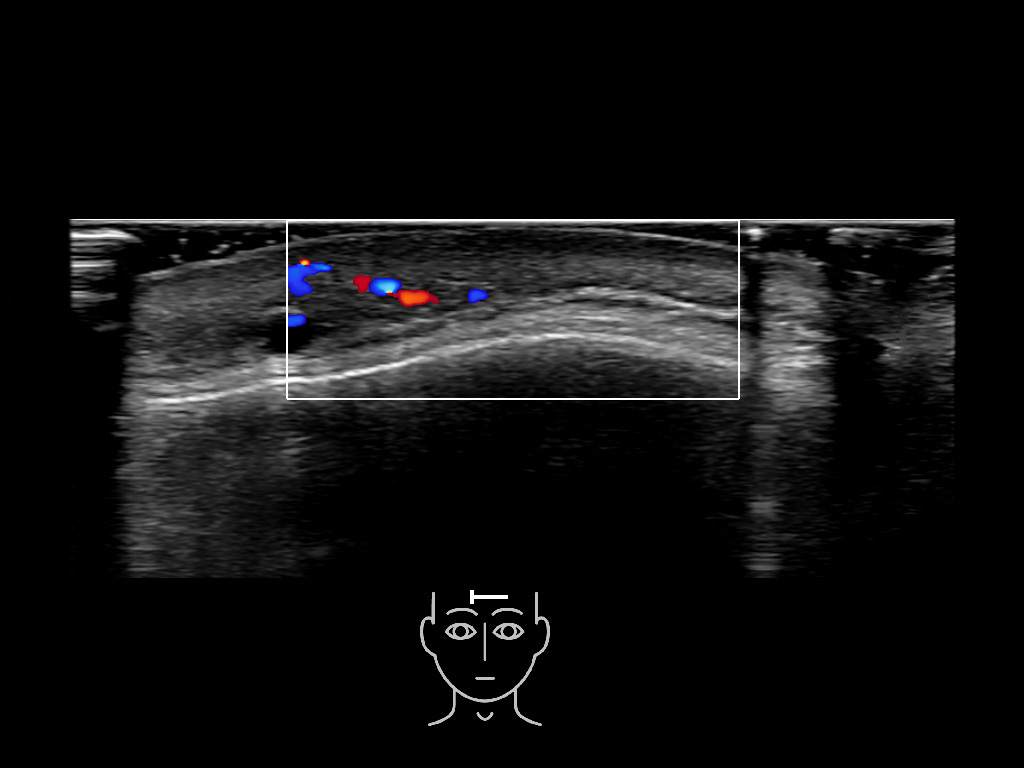

In this section you will learn more about the different layers of the face with the use of ultrasound. When you click on the secondary ultrasound image, you will see the different structures as an overlay. This will help to train yourself to recognize the different layers of the face.

Study the first image to recognize the different layers. If you are sure about the layers, swipe to the second image to view the answer (if applicable).